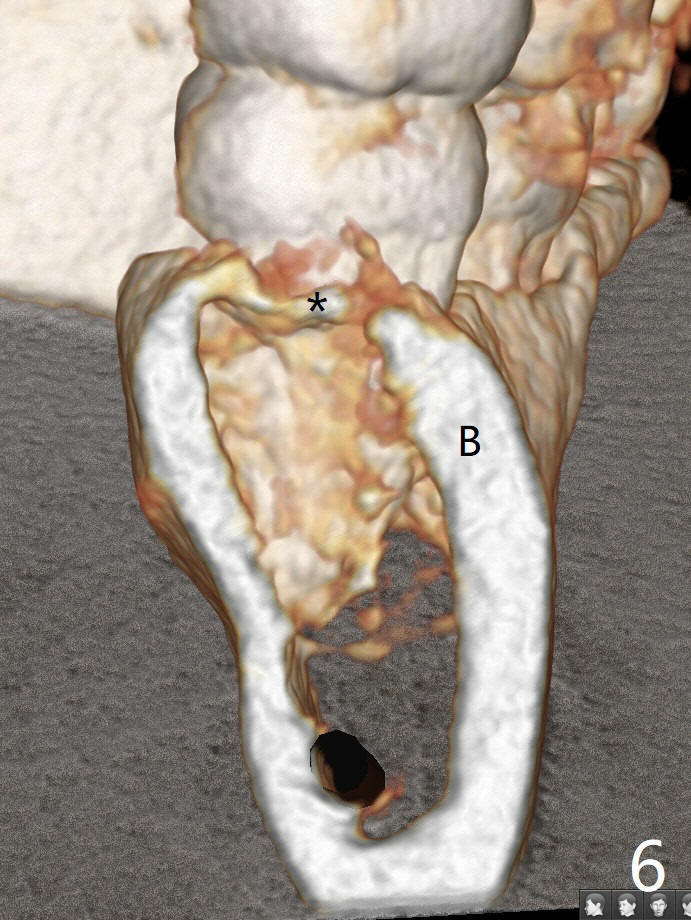

A 34-year-old lady requests extraction of #1, 16 and 32 (Fig.1). After incision for 32, surgical bur is used to create a purchase point to protect the thin bone between #31 and 32. The tooth is extracted with straight elevators and forceps. The socket is large single. Osteogen plug is placed with 4-0 plain gut suture (x4). There is cortical formation in the crest at #1, 16 and 32 three years postop (Fig.2-6 *, arrowheads). The advantage of Osteogen plug over Augma is easy placement with less risk of loss (by dissolving by saliva).